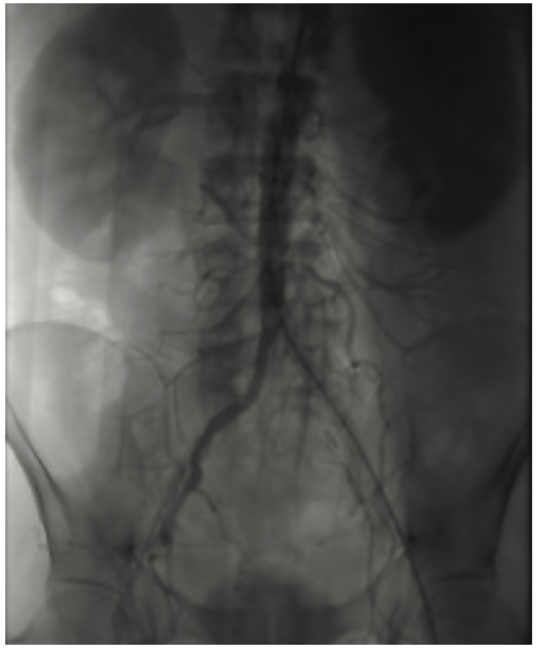

He clinically improved and on the second hospital day, underwent diagnostic cardiac catheterization. He did not have palpable radial pulses bilaterally; therefore, a femoral approach was used. His right external iliac artery and right common femoral artery were occluded. His distal aorta was heavily calcified with a high-grade eccentric stenosis. He also had a proximal 70%-80% left common iliac artery stenosis. Diagnostic coronary angiographic findings demonstrated a heavily calcified ostial 99% lesion in the right coronary artery (RCA) with significant calcium accumulation throughout the mid RCA. The left main coronary artery appeared heavily calcified, with a wedge-shaped filling defect suggesting a high-grade eccentric stenosis. The proximal left anterior descending (LAD) artery was very tortuous with a heavily calcified lesion at the first diagonal that extended into the ostium of the diagonal vessel. The circumflex artery was totally occluded. The patient’s ejection fraction based on ventriculography was 35% to 40%, with the posterior lateral wall being akinetic. He was extubated following the cardiac catheterization. Cardiothoracic surgery was consulted to provide an opinion regarding surgical revascularization. Due to his multiple comorbidities, he was felt to be high risk and not a surgical candidate. A plan for percutaneous revascularization was discussed with the patient. The nature and purpose of the procedure along with expected outcomes, together with the reasonably known risks were explained. He acknowledged that such disclosure of information had been made and that all questions asked about the procedure had been answered. He demonstrated understanding and legal capacity to consent and therefore, the written consent was obtained by his signature. The intervention was performed on hospital day 5. The patient was discharged home on hospital day 7.

Access: The patient had significant peripheral vascular disease with only one available access point in the left femoral artery. Both radial and right femoral arteries were significantly diseased, leaving only the left femoral artery available for access. The distal aorta was also moderately to severely stenosed and extended into the left common iliac, which was significantly stenosed (~70%) at the ostium of the vessel, yet patent enough to pass a wire and a diagnostic catheter. For this reason, hemodynamic support with an Impella (Abiomed) was not a practical option and not a part of the initial treatment planning. An intra-aortic balloon pump was made available and ready as a backup strategy if hemodynamic instability occurred.

With the left femoral artery being the only viable access, it was determined best not to stage the procedure. The plan was to treat all three vessels in one encounter using a 7 French (Fr) x 35 cm Brite Tip sheath (Cordis) in the left femoral artery, placing the sheath tip beyond the lesion into the abdominal aorta. Treatment of the stenosed common iliac would be considered for another day when patients recovery from the current procedure was complete.